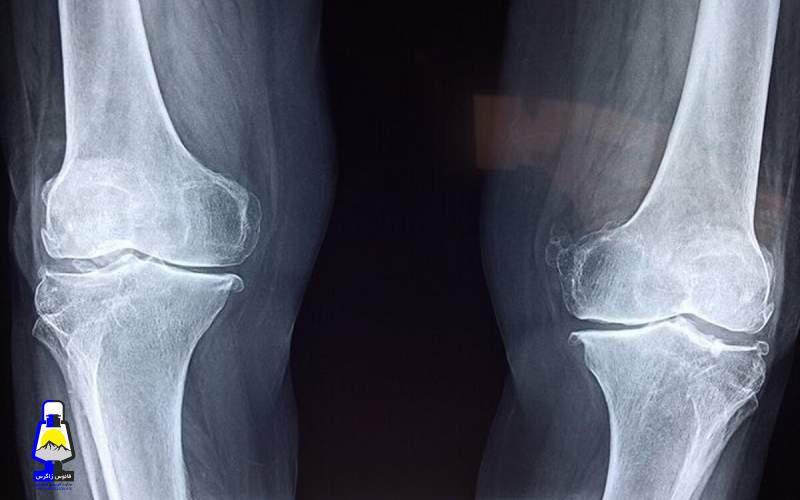

آسیب به استخوانها

نخستین نگرانی، تاثیر منفی بر سلامت استخوانهاست. مصرف نوشابه و الکل هر دو با کاهش تراکم مواد معدنی استخوان و افزایش خطر شکستگی مرتبط است. مصرف نوشابه بهدلیل وجود اسید فسفریک میتواند تعادل کلسیم و فسفر را بر هم بزند و خطر شکستگی لگن را افزایش دهد. مصرف الکل نیز با کمبود کلسیم، اختلالهای کبدی و کاهش ویتامین دی همراه است که همگی به تضعیف استخوانها منجر میشوند.